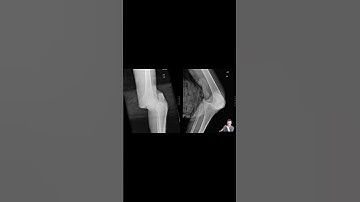

Traumatic Knee Dislocation Reduction